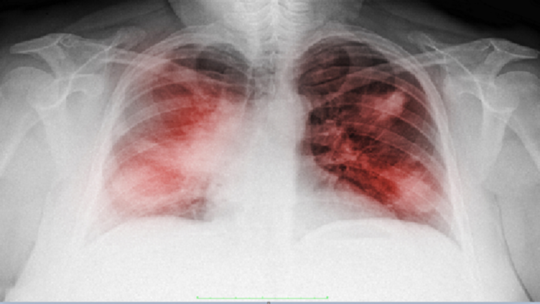

اكتشف علماء جامعة موسكو أن جرعات عالية من فيتامين В1 تؤثر سلبا في خلايا سرطان الرئة، دون أن تلحق أي أضرار بالخلايا السليمة.

ويشير بيان المكتب الإعلامي للجامعة، إلى أن "علماء جامعة موسكو اكتشفوا أن جرعات كبيرة من فيتامين В1 تؤثر سلبا في خلايا سرطان الرئة دون أن تؤثر في الخلايا السليمة. وفيتامين В1 يستخدم في مجال الطب على نطاق واسع في حالات مرض السكري وحالات قصور الكبد والكلى والقلب وأمراض أخرى".

وقد اختبر الباحثون هذه الفكرة في المختبر على خلايا سرطان الرئة البشرية وخلايا الرئة الظهارية السليمة التي تصاب عادة بالسرطان، أخذت من القرود. واتضح أن لفيتامين В1 تأثير مماثل لدواء سيسبلاتين الذي يستخدم غالبًا لعلاج سرطان الرئة.